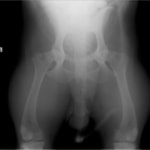

レッグぺルテス罹患症例の股関節のレントゲン写真

レッグペルテス病/無菌性大腿骨頭壊死症はトイ種やテリア種などの小型犬に好発し、5~8ヶ月齢の若齢期に多く発症します。大腿骨の先端(大腿骨頭)が、血液供給の障害により成長が阻害され、大腿骨頭の変形や壊死を起こす病気です。罹患動物は股関節の強い痛みのため、日常生活においては進行性の跛行(ケンケンをして歩く、足を地面に着かない等)の症状が認められます。肢を使わなくなるため筋肉量は減少し後肢は細くなります。

診断方法は主に触診と画像検査により行われます。触診では足を後方に伸ばし、疼痛の有無を調べます。レントゲン検査では、大腿骨頭や骨頸の骨密度の低下、大腿骨頭の辺縁部の変形、大腿骨頭や骨頸の亜脱臼等が認められることがあります。しかし発症初期では、レントゲン所見には異常が認められず、繰り返しのレントゲン撮影、CT検査を行う場合があります。